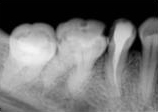

antes depois